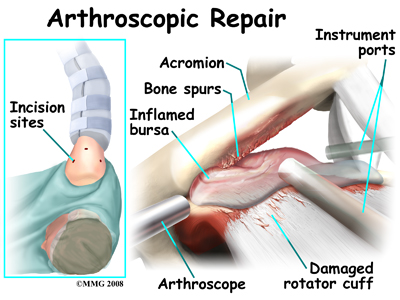

Closed Procedure Using Arthroscope

An arthroscope is a special type instrument designed to look into a joint, or other space, inside the body. The arthroscope itself is a slender metal tube smaller than a pencil. Inside the metal tube are special strands of glass called fiberoptics. These small strands of glass form a lens that allows one to look into the tube on one end and see what is on the other side - inside the space. This is similar to a microscope or telescope. In the early days of arthroscopy, the surgeon actually looked into one end of the tube. Today, the arthroscope is attached to a small TV camera. The surgeon can watch the TV screen while the arthroscope is moved around in the joint. Using the ability to see inside the joint, the surgeon can then place other instruments into the joint and perform surgery while watching what is happening on the TV screen.

The arthroscope lets the surgeon work in the joint through a very small incision. This may result in less damage to the normal tissues surrounding the joint, leading to faster healing and recovery. If your surgery is done with the arthroscope, you may be able to go home the same day.

To perform the acromioplasty using the arthroscope, several small incisions are made to insert the arthroscope and special instruments needed to complete the procedure. These incisions are small, usually about one-quarter inch long. It may be necessary to make three or four incisions around the shoulder to allow the arthroscope to be moved to different locations to see different areas of the shoulder.

A small plastic, or metal, tube is inserted into the shoulder and connected with sterile plastic tubing to a special pump. Another small tube allows the fluid to be removed from the joint. This pump continuously fills the shoulder joint with sterile saline (salt water) fluid. This constant flow of fluid through the joint inflates the joint and washes any blood and debris from the joint as the surgery is performed.

There are many small instruments that have been specially designed to perform surgery in the joint. Some of these instruments are used to remove torn and degenerative tissue. Some of these instruments nibble away bits of tissue and then vacuum them up from out of the joint. Others are designed to burr away bone tissue and vacuum it out of the joint. These instruments are used to remove any bone spurs that are rubbing on the tendons of the shoulder and smooth the under surface of the acromion and AC joint.